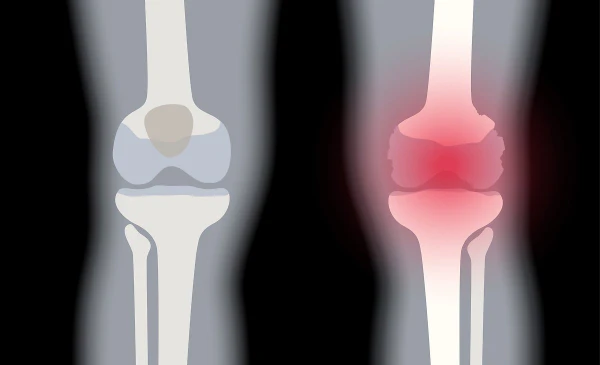

통풍이란 요산이 체내에 쌓여 관절에 염증을 일으키는 질병으로, 관절이 혹처럼 튀어나와 보일 정도로 심한 증상을 유발한다. 통풍이라 불리는 이 질병은 고통스럽고 찌르는 통증을 동반하며, 바람이 불면 더욱 심해지는 것이 특징이다. 이러한 고통은 주로 밤이나 새벽에 나타나며, 급성인 경우 일주일에서 한 달 동안 지속될 수 있다. 만성적인 경우에는 요산배설촉진제를 사용하여 치료된다.

통풍은 주로 체내에 과다 축적된 요산으로 인해 발생합니다. 요산은 우리가 섭취하는 다양한 음식이 소화되어 최종적으로 대사된 후 혈액에 녹아 있다가 소변으로 배출되는 물질입니다. 일반적으로 혈액 내에서 요산은 정상 수준을 유지하며 배설됩니다. 그러나 통풍 환자는 혈액 내 요산이 과다하게 증가합니다. 이러한 과다 축적된 요산은 결정체로 변화하고, 이러한 결정체가 관절 내에 침착하여 염증을 일으킵니다.

통풍을 적절히 치료하지 않을 경우, 발작성 관절염의 빈도가 증가하고 침범하는 관절 수도 더 많아지며, 회복에 필요한 시간도 증가합니다. 반복적인 관절염은 관절을 점차 손상시키며, 만성적인 관절염으로 진행될 수 있습니다. 또한 통풍성 결절이라 불리는 덩어리가 관절 주위나 피부 조직에 나타날 수 있습니다. 이러한 결절은 요산 결정체의 덩어리로 어느 부분에서든 형성될 수 있으며, 주로 팔꿈치, 귀, 손가락, 발가락, 발목 등에서 발생할 수 있습니다. 때로는 요로 결석을 형성하기도 합니다.